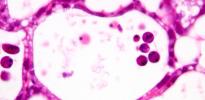

A novel mechanism of cell death that occurs in mammalian organisms has been revealed by researchers at the University of Cambridge. Read more at Cambridge Research News…